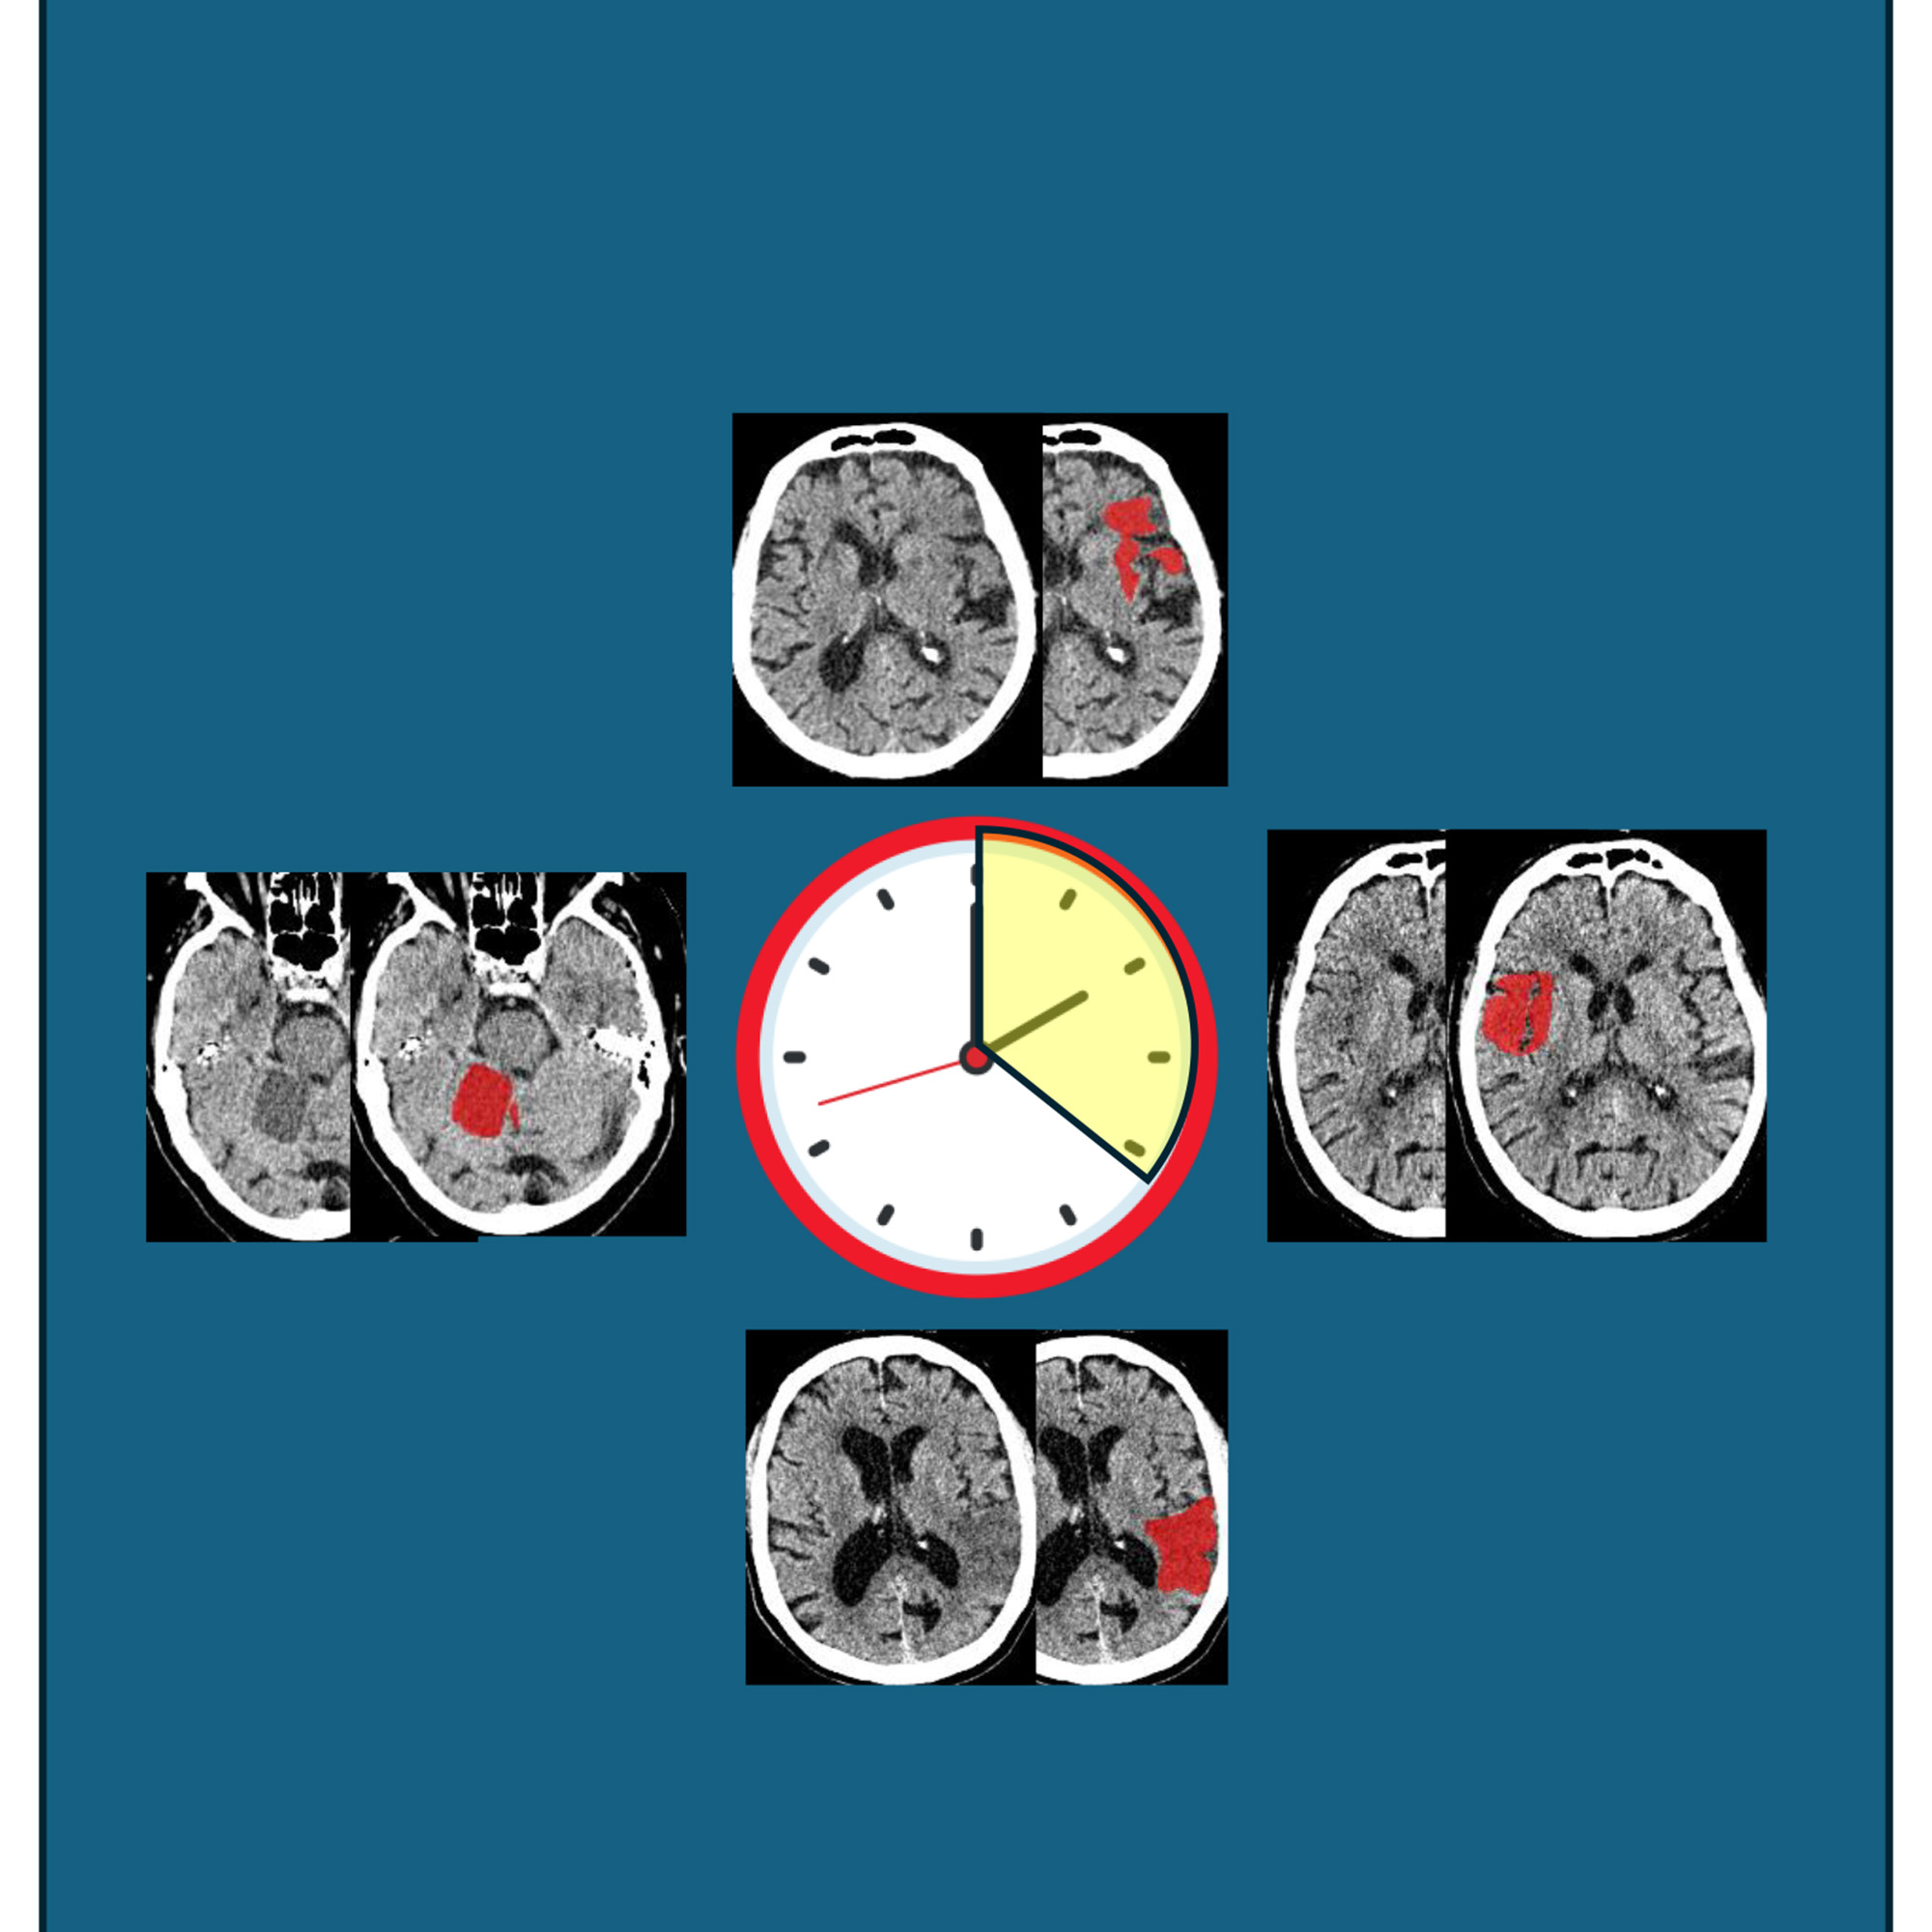

Bentley is also Clinical Director of the university’s Network of Excellence in Rehabilitation Technology, a cross-disciplinary network of biomedical scientists, clinicians, physical scientists and engineers. He led a team of researchers who trained an AI model with 780 separate CT scans, which showed a range of brain patterns at different times following a stroke. “The images are black and white and shades of grey,” says Bentley. “In the first minutes following the stroke, lesions are so faint as to be almost invisible, but then gradually get darker. This means in those crucial first few hours they can be missed

“The AI did what we expected, but significantly better than we’d hoped,” says Bentley. “We thought it was the intensity of the lesion that held most of the information, but actually the AI revealed that accounting for other imaging features can double the accuracy.”

The model was twice as accurate at predicting the time of stroke onset – which, if used in practice, will reduce the risk of patients being given treatment at the wrong time. “Around 100,000 people annually in the UK suffer a stroke, of which around 10,000 are identified as eligible for these treatments,” says Bentley. “Accurately identifying the time of onset could increase this by about 50 per cent. We expect – and very much hope – that this model will be copied or developed by companies already producing similar types of clinical software, to piggyback on top of it. We think it’ll make a huge difference.”